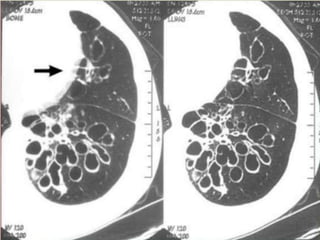

 “Tramlines” or “honeycombing” represents

dilated, thickened bronchial walls

 Signs on CXR include the identification of

parallel linear densities, tram-track opacities, or

ring shadows reflecting thickened and

abnormally dilated bronchial walls. These

bronchial abnormalities form a spectrum from

subtle or barely perceptible 5-mm ring

shadows to obvious cysts. Tubular branching

opacities conforming to the expected bronchial

branching pattern may result from fluid or

mucous filling of bronchi

dilated, thickened bronchial walls.